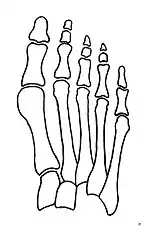

Primus varus deformity

Primus varus deformity is the leaning of the first metatarsal bone away from the second metatarsal and towards the opposite foot (Fig. 1). As it leans over, its head sticks out to form the bunion bump and it also widens the forefoot to cause shoes feeling too tight. Thus when bunion pain becomes unmanageable, surgical correction is to narrow the forefoot by repositioning of the first metatarsal head back to its normal position. This can be done by osteotomy (bone-breaking), soft tissue (non-osteotomy) or fusion techniques.